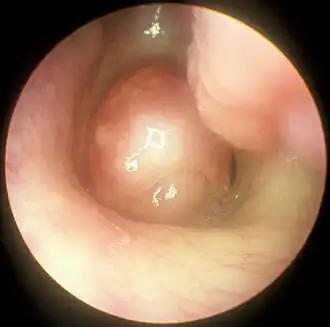

Pólipo nasal em imagem captada por nasofibroscopia.

Pólipo nasal, também chamado polipose nasossinusal (PN) e pseudotumor nasossinusal, são formações polipóides não neoplásicas, pedunculadas e edematosas observadas nas cavidades nasais e seios paranasais em decorrência de um processo inflamatório crônico da mucosa nasal.[1][4][5][6] Geralmente de ocorrência bilateral, seus sintomas incluem obstrução nasal constante com dificuldade para respirar pelo nariz, perda do olfato, diminuição do paladar e secreção nasal anterior e posterior. Cefaleia e dor facial podem ocorrer, mas não são frequentes.[1][4] Entre as complicações geradas por essa patologia, uma das principais é a sinusite.[7][2]